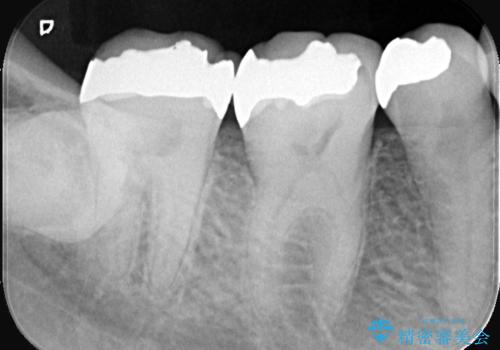

- 以前治療した右下7番(奥歯)のインレー(詰め物)が欠けてしまったことを主訴にご来院されました。診査の結果、残っている歯質が少なく、通常の詰め物では再び歯が割れてしまう破折リスクが高いと診断しました。このリスクを回避し、強い咬合力に耐えられるよう、歯全体を覆うクラウン(被せ物)による修復を提案。素材には、強度と適合性に優れたPGA(白金加金)クラウンを選択し、長期的に安定した奥歯の機能回復を目指しました。

治療ではまず、欠けた部分を修復し、歯全体を均一に形成しました。その後、PGA(白金加金)クラウンを作製・装着しました。

強度: 非常に高い強度を持つため、奥歯の強い咬合力にも耐え、歯の破折を効果的に防ぎます。

適合性: 歯への適合性が非常に高く、精密に隙間なく装着できるため、被せ物の下からの二次的な虫歯のリスクを最小限に抑えられます。